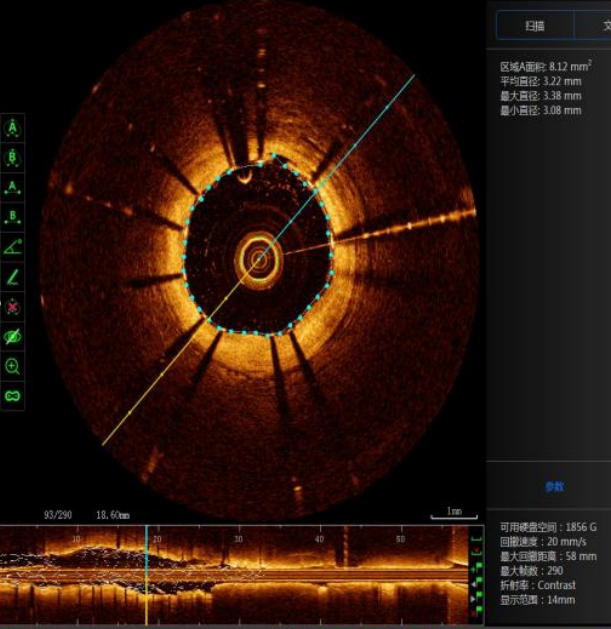

术中,手术团队通过新一代国产光学相干断层(OCT)检查,可直观识别到王先生前降支中段最狭窄病变处最小管腔面积在植入支架后由2.2mm²增至8.12mm²,支架全程贴壁良好,支架边缘未见夹层、血肿。

(支架植入后OCT检查提示支架贴壁良好)